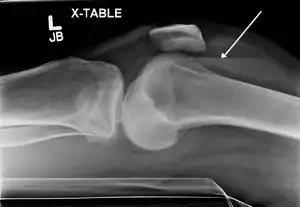

| A severe tibial plateau fracture with an associated fibular head fracture | |

A tibial plateau fracture seen on X-ray